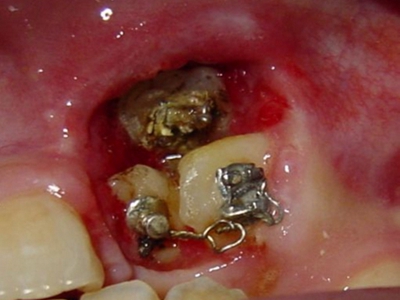

阻生牙是指由于邻牙、骨或软组织的阻碍而只能部分萌出或完全不能萌出,且以后也不能萌出的牙。引起牙阻生的成因,主要是由于颌骨缺乏足够的空间容纳全部恒牙。常见的阻生牙为下颌第三磨牙、上颌第三磨牙及上颌尖牙。

阻生牙可反复引起冠周炎,或引起邻牙牙根吸收和破坏,位置不正,不能完全萌出,好发部位是上、下颌第三磨牙。